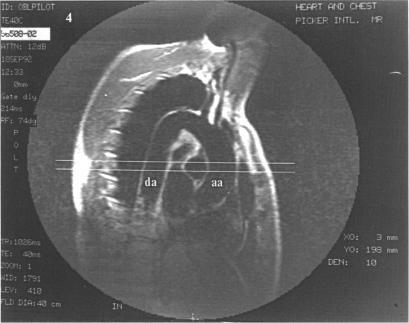

Magnetic resonance imaging (MRI) is a versatile technique for examination of the cardiovascular system but only recently has assessment of myocardial ischaemia in coronary artery disease (CAD) become possible, for example by demonstrating abnormalities of regional ventricular contraction during stress. Global ventricular function during stress was assessed by MRI of aortic flow, which has not been previously attempted.

Novel MRI sequences and analysis systems were used to measure the following variables during staged dobutamine infusion to 20 micrograms/kg/min: stroke volume, cardiac output, cardiac power output, peak flow, peak flow acceleration, aortic back flow, and flow wave velocity. Heart rate, blood pressure, double product, and maximum tolerated dobutamine dose were also measured. Multiple regression analysis was used to compare changes during stress with 201TI tomography.

All parameters except for stroke volume and diastolic blood pressure increased in the controls. In the patients with CAD a significant relation was shown between the extent of reversible ischaemia and the change in peak flow acceleration (P < 0.00001), peak flow (P = 0.002), cardiac power output (P = 0.036), maximum dobutamine dose (P = 0.039), and systolic blood pressure (P = 0.04). Peak flow acceleration accounted for 58.4% of the variation in reversible ischaemia, and after allowing for this, only cardiac power output remained independently predictive adding a further 4.2% to the model (adjusted r2 = 0.626). A decrease in peak flow acceleration with an increase in dobutamine infusion indicated moderate or severe ischaemia (chi 2 = 10.2, P = 0.017).

MRI may be used to assess variables of aortic flow during stress, which includes acceleration with high temporal resolution. Peak flow acceleration was the most sensitive indicator of the effect of ischaemia on global ventricular function.